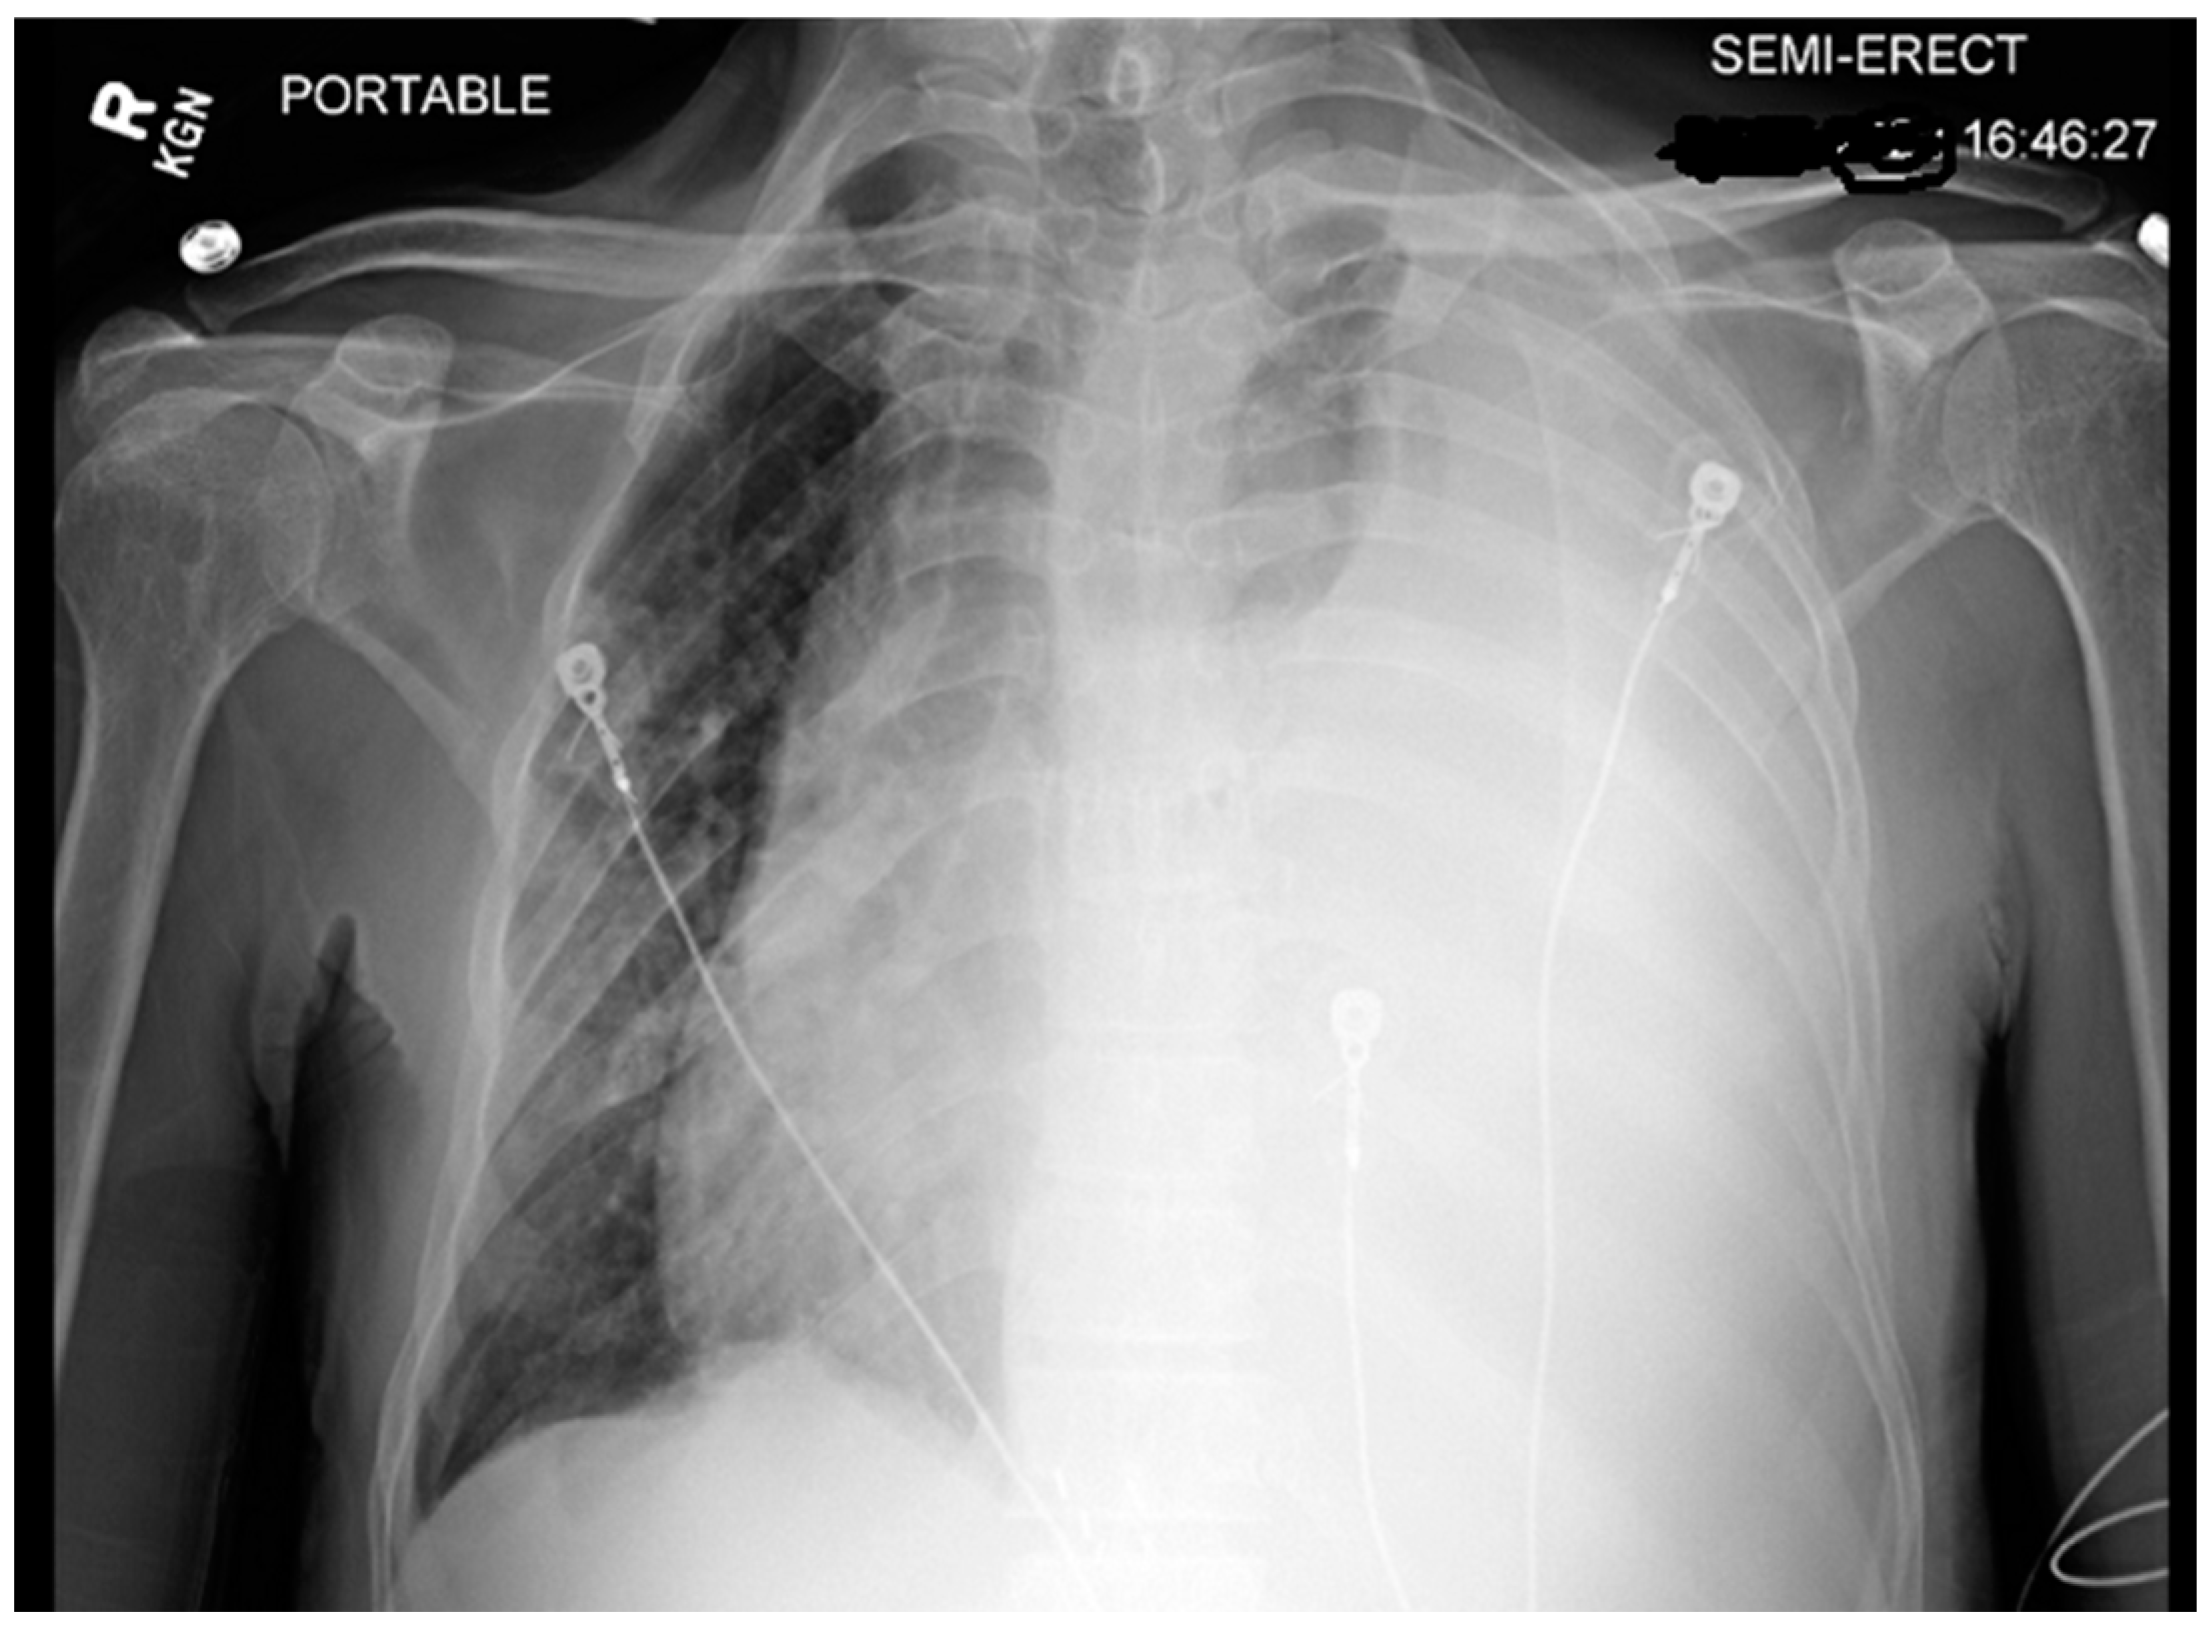

Chest X-ray (CXR) and computed tomography (CT) chest revealed a massive left-sided pleural effusion with mediastinal shift, concerning for tension hydrothorax as depicted in Figure 2 and Figure 3. Additionally, the CT scan revealed pleural nodularity with calcification on the left side without surrounding osseous involvement.

Figure 2. X-ray demonstrating large left-sided pleural effusion with tracheal deviation and mediastinal shift to the right.